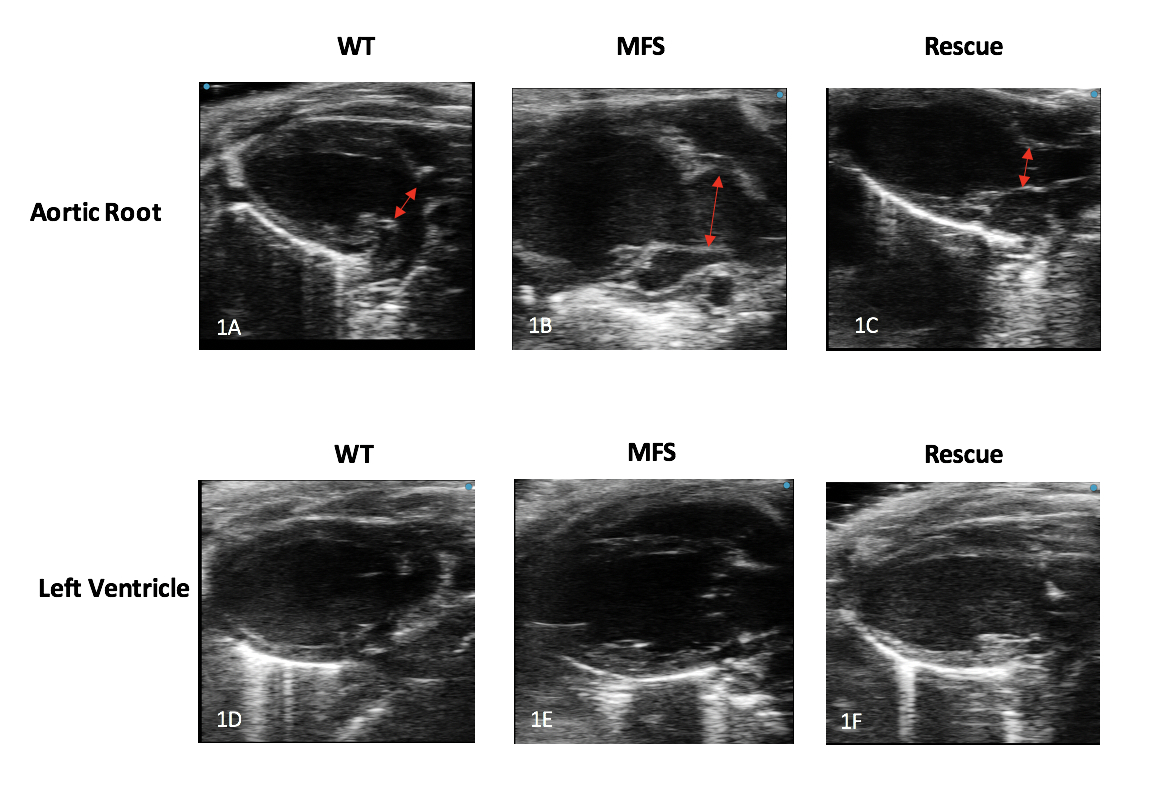

We generated a conditional smooth muscle cell deletion of Adamts6 in a known chronic MFS mouse model. Echocardiograms were completed in MFS mice with Adamts6 inactivation (“Rescue” mice), non-disease wild type controls (“WT” mice), and MFS mice. Measurements of aortic root size, outflow velocity, left ventricular end diastolic volume (LVEDV), ejection fraction (EF), and mitral E/A ratio were completed to assess cardiac phenotype. Histological sections were then created and used to further assess differences in aortic composition among groups.

Echocardiography revealed a statistically significant difference in aortic root diameter between WT and MFS mice (Mean difference: 0.77 mm +/- 0.16 mm, p <0.001) and between MFS and Rescue mice (Mean difference: 0.62 mm +/- 0.16 mm, p = 0.002). Pulsed-wave doppler across the aortic valve also showed significantly reduced velocity in Rescue vs. MFS mice (Mean difference: 304.4 mm/sec +/- 103.2 mm/sec). There was a significant reduction in mitral valve E wave to A wave ratio when comparing WT and MFS mice (Mean difference: 0.49 +/- 0.18, p = 0.05). Importantly, there was no significant differences in aortic root size, outflow velocity or mitral E/A ratio between WT and Rescue mice (Figures 1 and 2). There were no statistical differences in LVEDV and EF among the three groups. Histologically, Rescue mice sections resembled those of WT mice, with decreased elastin breaks and proteoglycan and collagen accumulation compared to the MFS cohort (Figure 3).